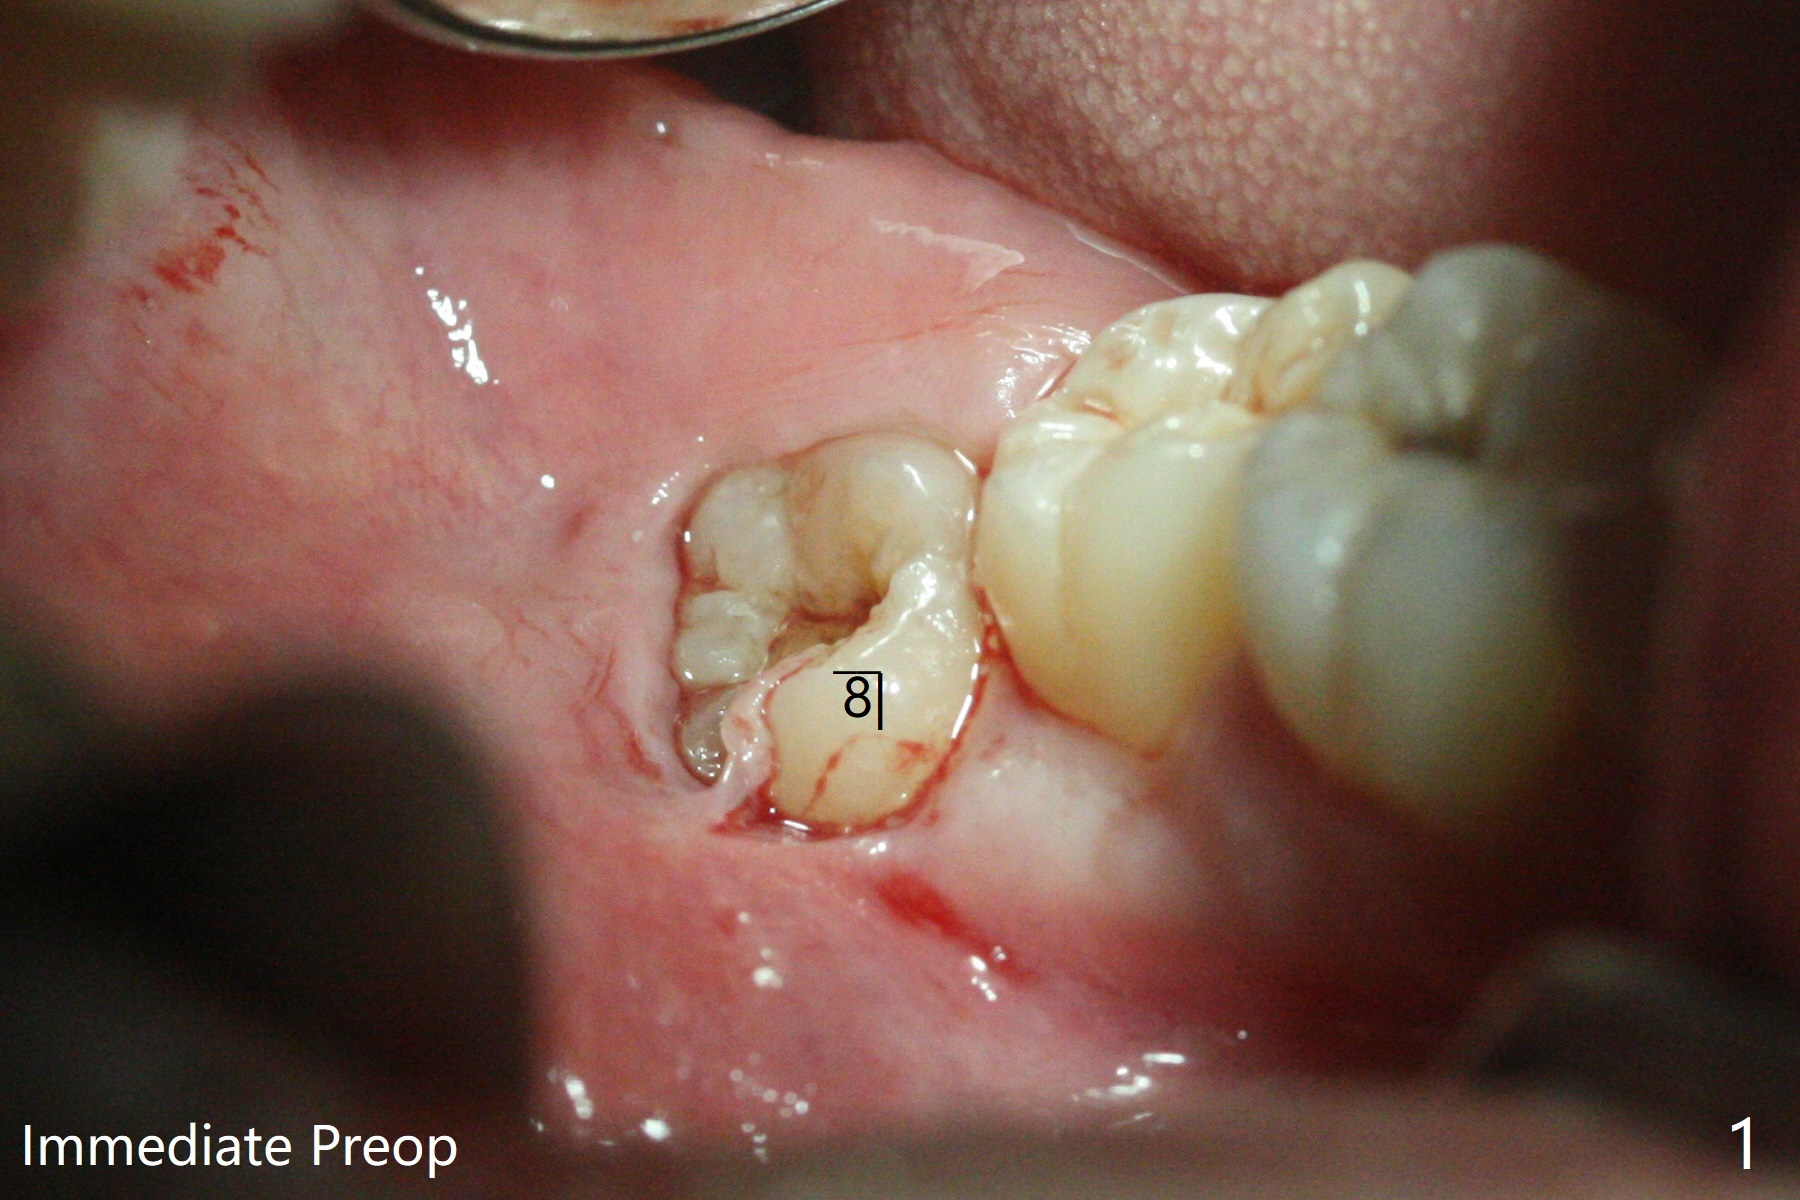

30岁男下颌深洗后,局部浸润麻醉,准备拔除颊侧阻生智齿(图一至三),每个牙槽窝放置0.5cc骨水泥(Bone Cement (Bond Apatite from Augma)),覆盖半块胶原塞,4-0铬羊肠线缝合(图四)。